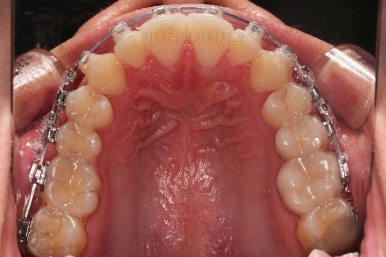

초진 시 입안의 모습입니다.

앞니가 약간 삐뚠 것 말고는 큰 문제는 없어보이네요.

장치를 부착했습니다.

이번 부산연제구교정 환자분이 선택한 장치는 엠파워 클리어라고 하는 자가결찰 세라믹 장치입니다.